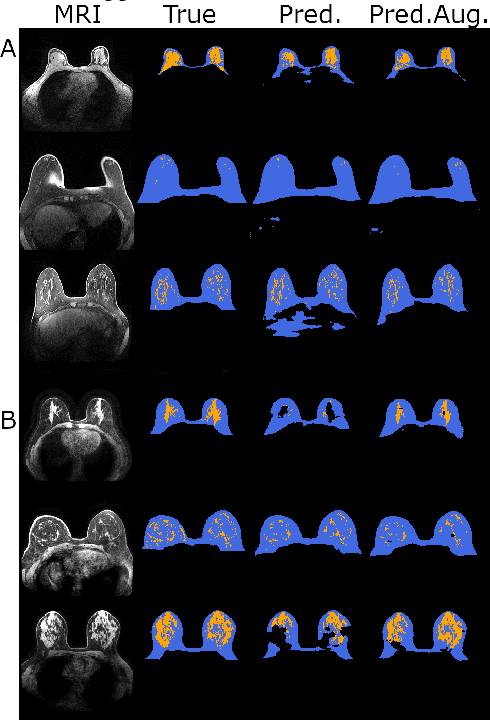

Abstract:Deep learning (DL) models in medical imaging face challenges in generalizability and robustness due to variations in image acquisition parameters (IAP). In this work, we introduce a novel method using conditional denoising diffusion generative models (cDDGMs) to generate counterfactual magnetic resonance (MR) images that simulate different IAP without altering patient anatomy. We demonstrate that using these counterfactual images for data augmentation can improve segmentation accuracy, particularly in out-of-distribution settings, enhancing the overall generalizability and robustness of DL models across diverse imaging conditions. Our approach shows promise in addressing domain and covariate shifts in medical imaging. The code is publicly available at https: //github.com/pedromorao/Counterfactual-MRI-Data-Augmentation